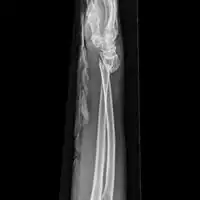

Side view of displaced fractured radius and ulna at wrist